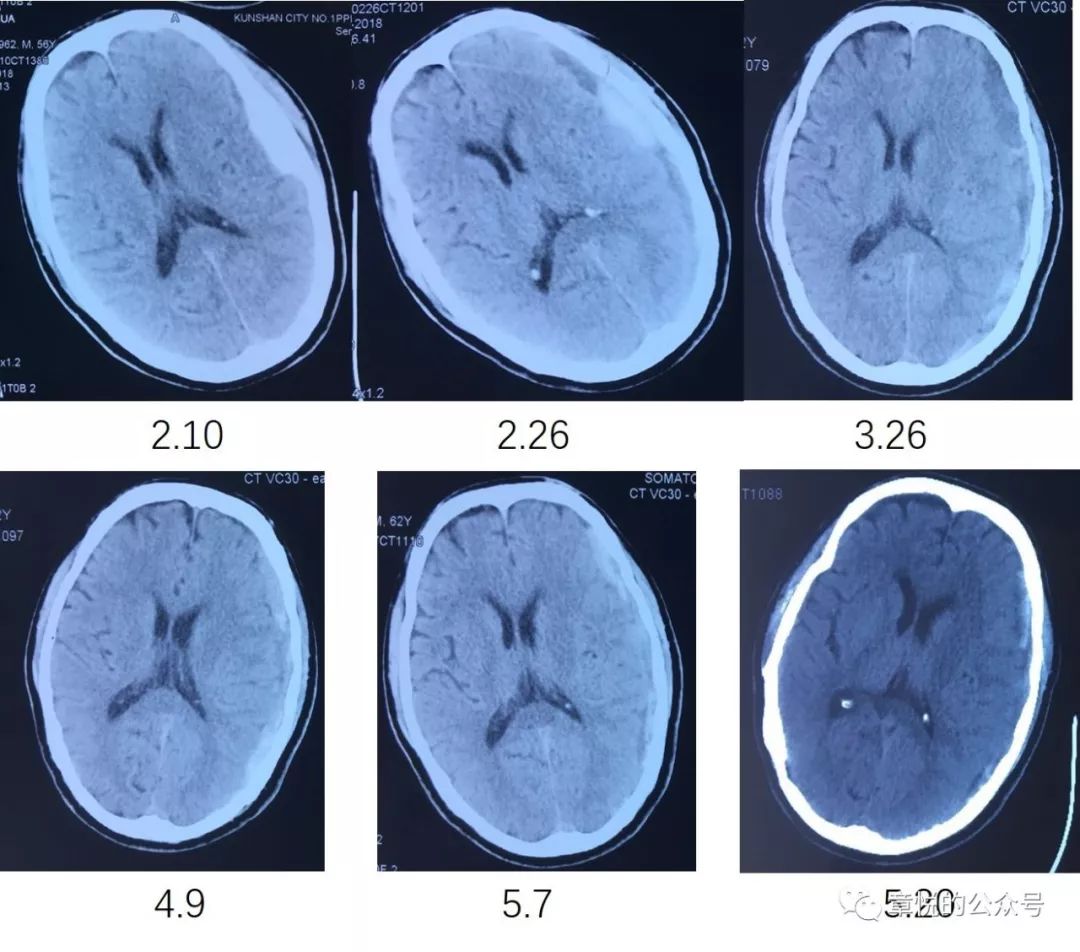

我今天讲述的这例慢性硬膜下血肿由急性者迁延所致,3个月来血肿没有大变化(图1),然而临床症状却突然加重了。

图1. 患者3个月来硬膜下血肿始终没有吸收,1个月前血肿影密度较前增高。

患者老年男性,3个月车祸头部受伤,当时除头痛没有其他症状,到当地医院行CT见左侧硬膜下血肿,因出血量不大,所以神经外科建议保守治疗,3个月中患者几次CT未见血肿吸收,但也没觉得什么不适。1周前患者开始出现头晕和左侧头痛,之后逐步出现意识混乱,言不达意,在入院前2天出现癫痫频繁发作,一天发作几十次,但头颅CT上血肿量并无增多,神经外科仍建议继续保守治疗。